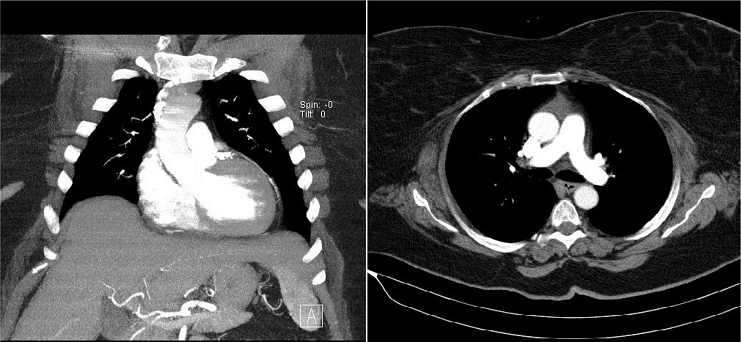

Twenty-one obese patients underwent mini-AVR via central cannulation between 2017 and 2021. All procedures were performed by two experienced heart valve surgeons. Sutureless bovine pericardial aortic prostheses (Perceval S, Liva Nova Sorin, Italy) or stented bovine pericardial aortic prostheses (Crown PRT, Liva Nova Sorin, Italy) were used. Patients’ age ranged from 58 to 82 years, with a mean age of 69.4±7 years. Obesity was defined as a body mass index (BMI) >30 kg/m2. Obese patients with isolated severe aortic valve stenosis or regurgitation were included. Exclusion criteria included a history of right pleurisy or pleural effusion with adhesion formation, chest wall deformities, previous major cardiac surgery involving pericardium opening, right-sided thoracic surgery, porcelain aorta, aneurysmal dilatation or ascending aortic dissection (≥4.5 cm) and concomitant significant coronary artery stenosis or other valve disease. The diagnosis of aortic valve disease was made by cardiologists with transthoracic echocardiography. Decisions for surgery were made at the Cardiology-Cardiovascular Surgery council. The American College of Cardiology and American Heart Association guideline published on 2014, titled “Guideline for the Management of Patients with Valvular Heart Disease”[10], was followed. All patients underwent computed tomography scan during the preoperative period, and patients were considered for this procedure if the ascending aorta was rightward (more than half was located to the right of the right sternal border) at the level of the main pulmonary artery (Figure 1). All patients had severe aortic stenosis.